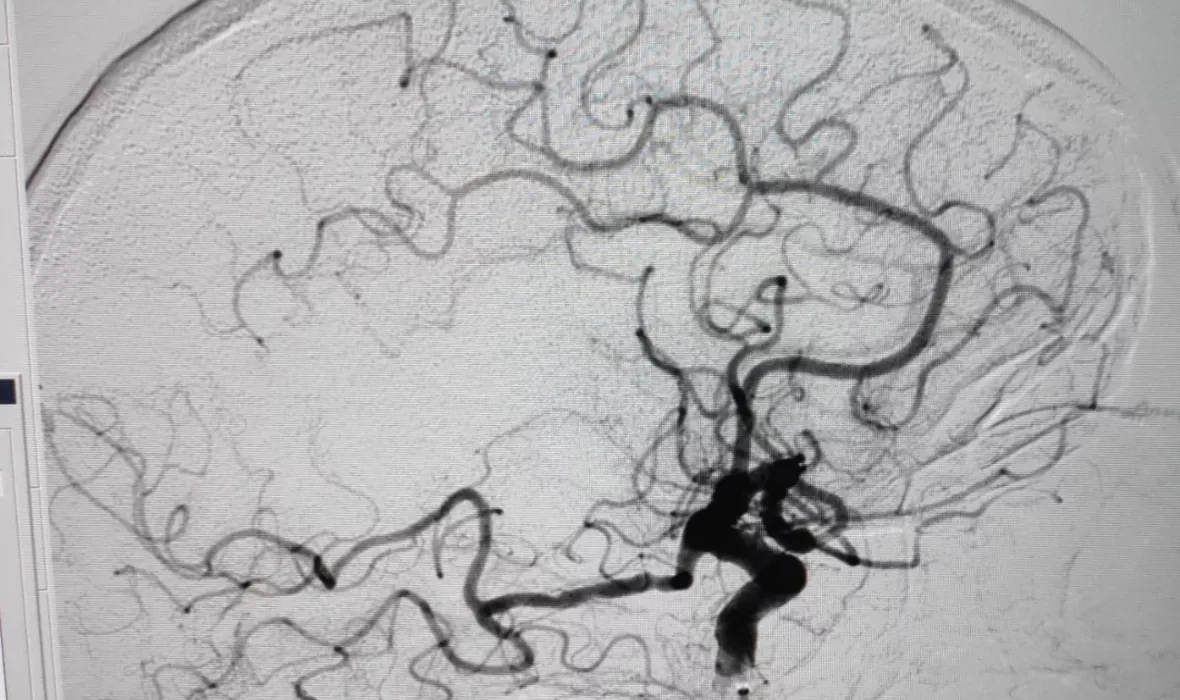

Els serveis de Neurologia, Radiologia (a càrrec de l'IDI) i Anestesiologia de l’Hospital Universitari de Girona Dr. Josep Trueta han ampliat l’horari d’atenció a pacients que han patit un ictus isquèmic agut amb oclusió arterial de gran vas per un trombe i amb tractaments de teràpia endovascular (trombectomies mecàniques), que ha passat de 12 h diàries els dies laborals (de 8 h a 20 h) a 12 h, els 365 dies de l’any. El procediment consisteix en la introducció d’un catèter en una artèria del pacient per arribar fins al coàgul que l’obstrueix –i que ha produït l’ictus– i poder-lo extreure. El procediment es va començar a fer de manera puntual l’octubre de 2018, però va ser a partir del 29 de setembre de 2019 que es va iniciar de manera continuada i en un horari fix. El 21 de març passat, just a plena pandèmia, es va decidir ampliar l’horari als caps de setmana i festius per evitar traslladar fora de la Regió Sanitària de Girona els pacients que requerien una trombectomia mecànica dins d’aquest horari. Si es produeix algun cas fora d’aquest horari, el pacient haurà de continuar essent derivat a l’Hospital Universitari Germans Trias i Pujol de Badalona.

Des que es va ampliar l’horari, el 21 de març, s’han fet 14 trombectomies, 7 de les quals han estat durant l’abril, el mes que ha acumulat més casos fins ara. Abans de l’ampliació horària s’havien fet 11 trombectomies durant aquest 2020 (des de l’1 de gener fins al 20 de març), 39 durant tot el 2019 i 8 durant el 2018. Aquests procediments es fan en una sala equipada amb tecnologia específica: la sala d’intervencionisme. En el 85 % dels 72 casos que s’han atès s’ha aconseguit una recanalització arterial cerebral i s’ha pogut extreure el trombe que ocloïa el vas.